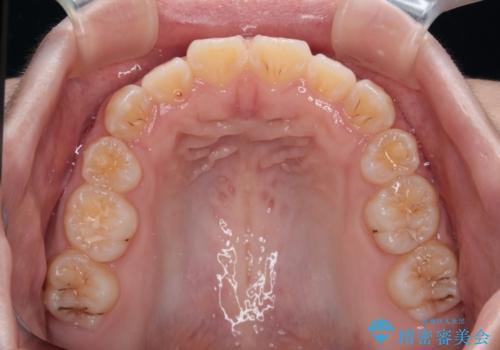

当初は舌のトレーニングがうまくできていなかったのですが、途中から奏効し、非常に短い期間で治療を終えることができました。